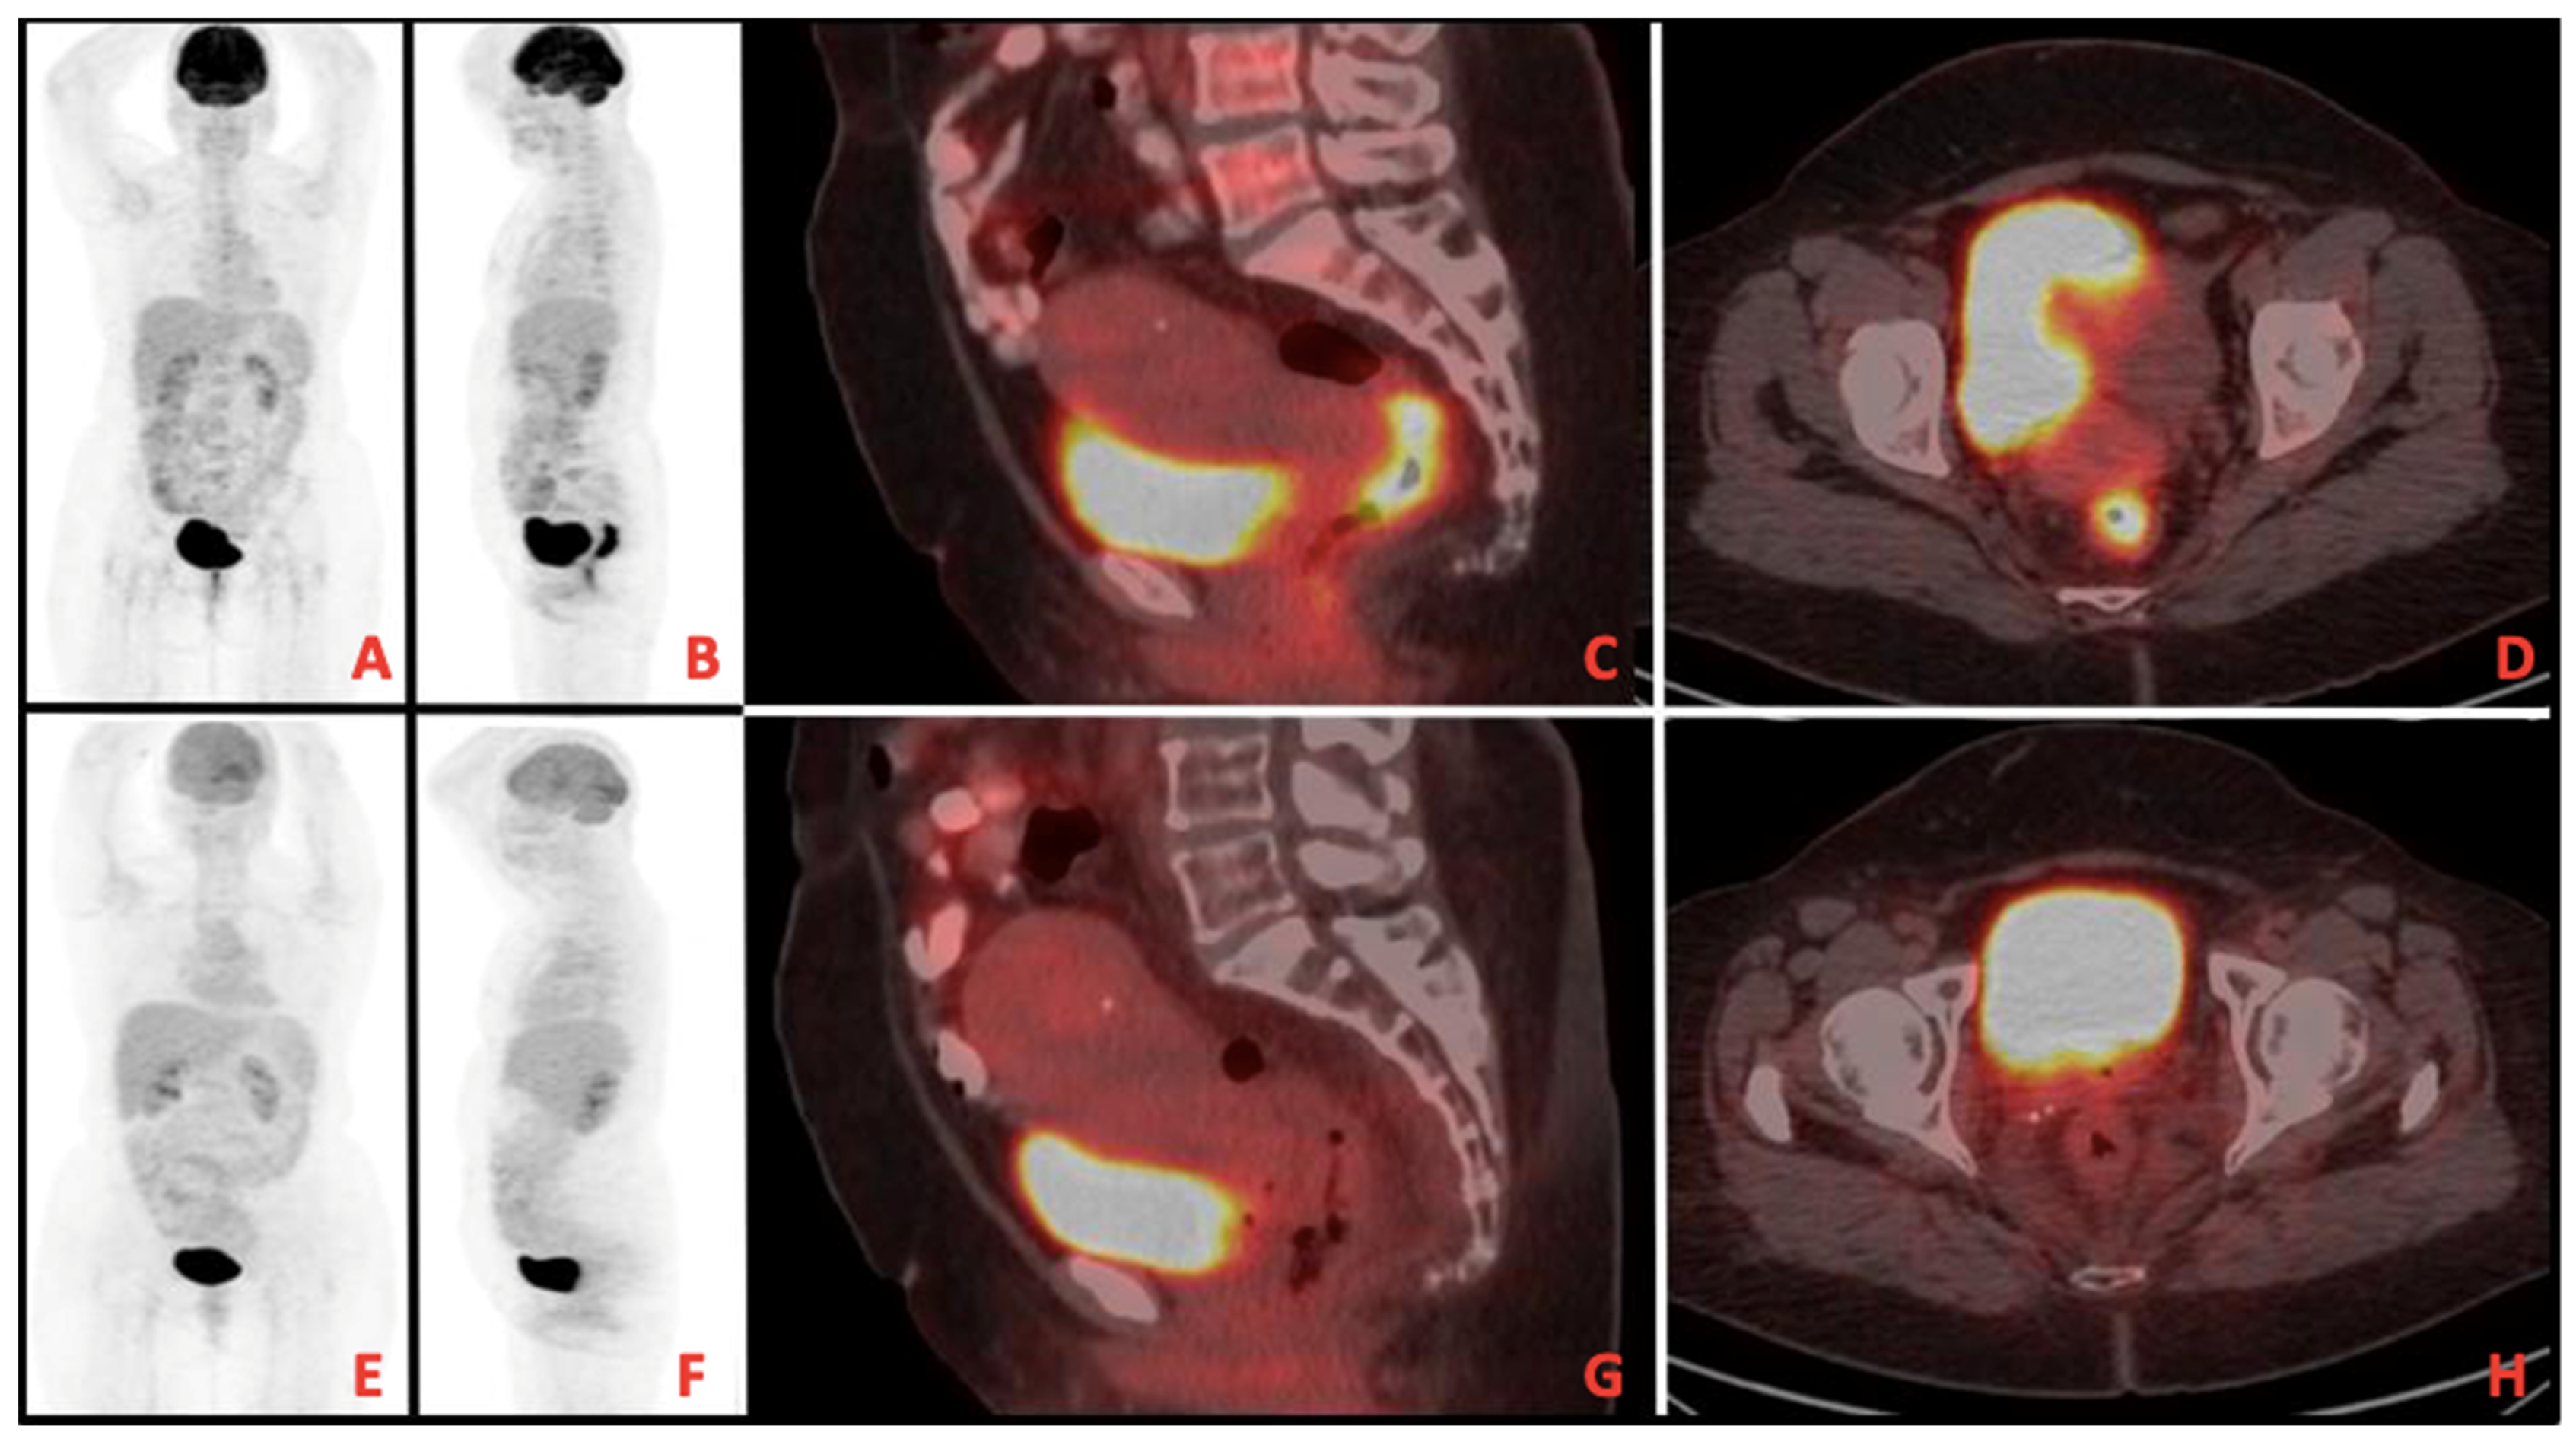

A total of 13 patients evaluated as cCR after TNT was completed were followed up with NOM. Figure 1 shows MRI images of a patient with complete response, and Figure 2 shows PET/CT images. It shows that 39 patients underwent surgery, and 8 of them had pCR. A total of 9 patients had ypT0 (one of them was ypT0N1), 1 had ypT1, 6 had ypT2, 21 had ypT3, and 1 had ypT4. In addition, 27 patients had no pathologically involved lymph nodes (ypN0), 9 had ypN1, and 2 had ypN2. These findings and tumor regression grading distribution are summarized in Table 3.

Figure 1. (AD) Pretreatment imaging, (EH) Posttreatment imaging on magnetic resonance imaging (MRI).